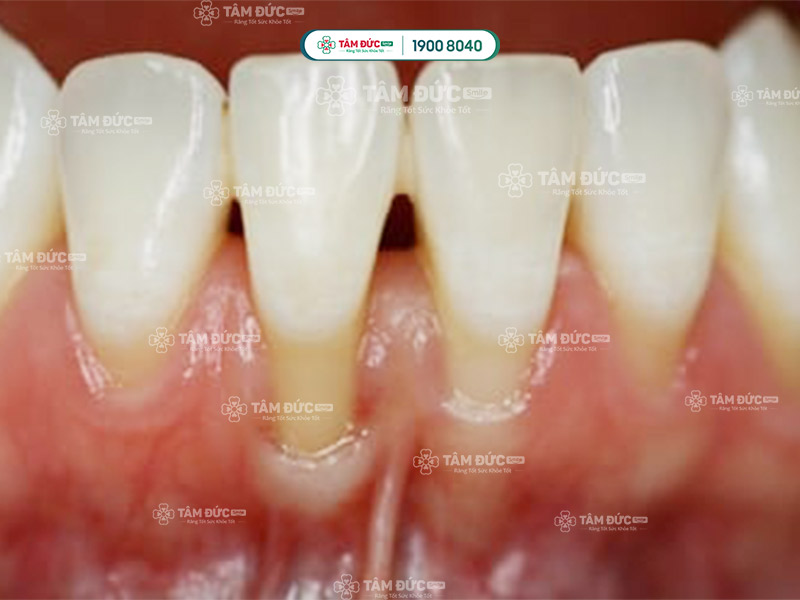

2.1. Răng nhạy cảm do lợi bị thoái hóa

Lợi là phần mô mềm bao phủ chân răng và xương hàm. Lợi khỏe mạnh sẽ bao phủ toàn bộ chân răng, ngăn chặn các tác nhân bên ngoài tiếp xúc với ngà răng. Khi lợi bị thoái hóa, nướu sẽ bị tụt xuống, lộ ra phần chân răng. Khi đó, ngà răng sẽ tiếp xúc trực tiếp với các tác nhân bên ngoài, đặc biệt là thức ăn nóng, lạnh, chua, ngọt, dẫn đến làm răng nhạy cảm.

Lợi bị thoái hoá làm lộ ngà răng